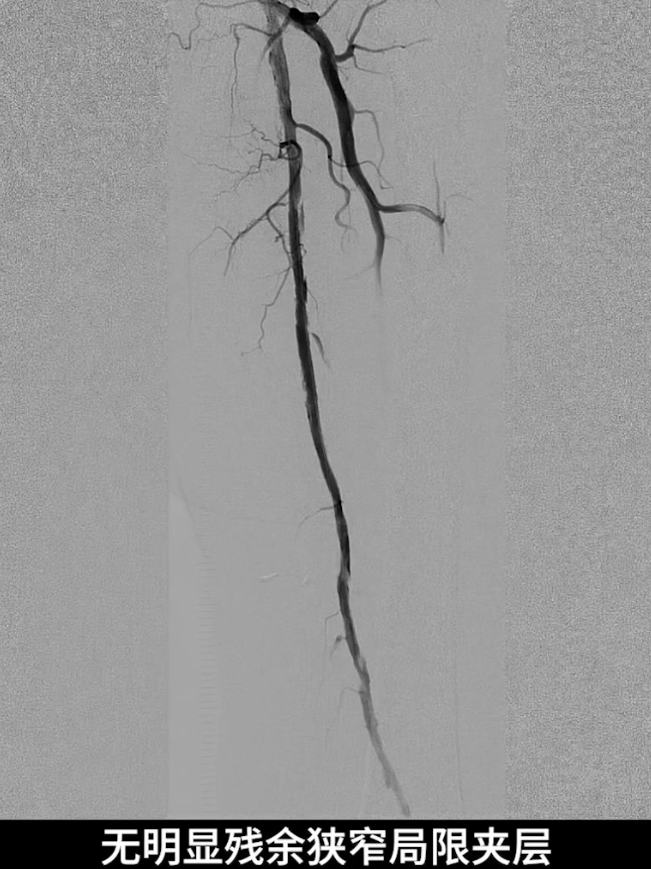

术后造影验证:股浅动脉管腔恢复通畅,无明显残余狭窄,局限夹层未对血流造成影响,无需植入补救性支架;膝下腓动脉流出道通畅,胫后动脉至足底动脉血流连续,足部血流灌注显著改善。